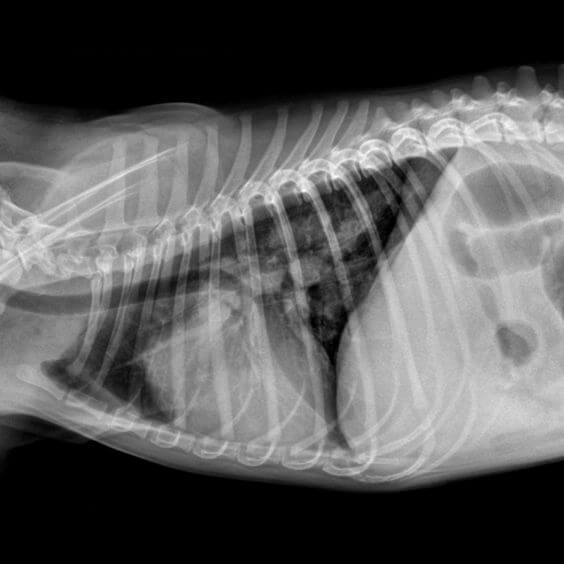

Ir dažādas metodes, kā apstiprināt plaušu tārpu invāziju, un veterinārārsts var izvēlēties izmantot tās visas, jo plaušu tārpu infekciju ir grūti diagnosticēt. Veterinārārsts var veikt ātros testus uz vietas, bet plaušu tārpus bieži var noteikt tikai pēc četrām līdz astoņām nedēļām pēc inficēšanās. Dažreiz plaušu tārpi ilgstoši paliek neatklāti. Plaušu tārpu diagnostikai izmanto fekāliju paraugus, plaušu šķidrumu, asins analīzes un rentgenoloģisko izmeklēšanu. Vislabāk noteikt, vai jūsu suns ir inficēts, var šo testu kombinācija, tādēļ, ka viens tests var nebūt pilnīgi uzticams atkarībā no parauga veida un infekcijas stadijas. Plaušu tārpu infekcijas ārstēšana būs atkarīga no infekcijas stadijas. Jo ātrāk tiek uzsākta ārstēšana, jo ātrāk jūsu suns atveseļosies. Problēmas rada fakts, ka suņiem bieži nav acīmredzamu klīnisko pazīmju, kamēr infekcija nav attīstījusies. Plaušu tārpu ārstēšanai un profilaksei ir nepieciešami īpaši medikamenti, kas atšķiras no parastajiem suņu attārpošanas līdzekļiem. Jautājiet savam veterinārārstam par regulāru plaušu tārpu profilaksi kopā ar parasto pretparazītu ārstēšanu.